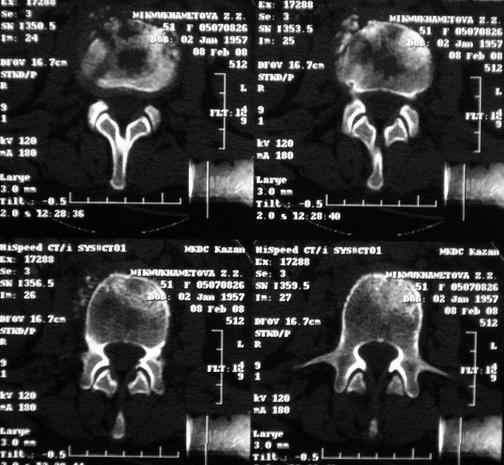

Re: Требуется телеконсультация Вертебролога

MRI через три недели